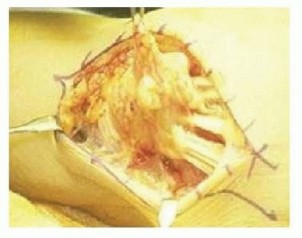

Tophus Excision and Tenosynovectomy

- Positioning and Anesthesia: The patient is positioned supine with the arm on a hand table. Regional anesthesia (axillary or supraclavicular block) is preferred. A well-padded pneumatic tourniquet is applied.

- Approach: Incisions should be planned to allow extensile exposure while preserving vascularity to the skin flaps. Tophi often adhere intimately to the dermis; meticulous dissection is required to prevent full-thickness skin necrosis.

- Debridement: The chalky, toothpaste-like MSU deposits are curetted and irrigated. Complete excision is often impossible without sacrificing vital structures. The goal is debulking to relieve pressure, not oncologic-level clearance.

- Tendon Management: If the flexor or extensor tendons are heavily infiltrated, a meticulous tenosynovectomy is performed. If a tendon is ruptured (e.g., EPL), primary repair is rarely possible due to substance loss and tissue friability. Tendon transfers (e.g., Extensor Indicis Proprius to EPL) are the preferred reconstructive option.